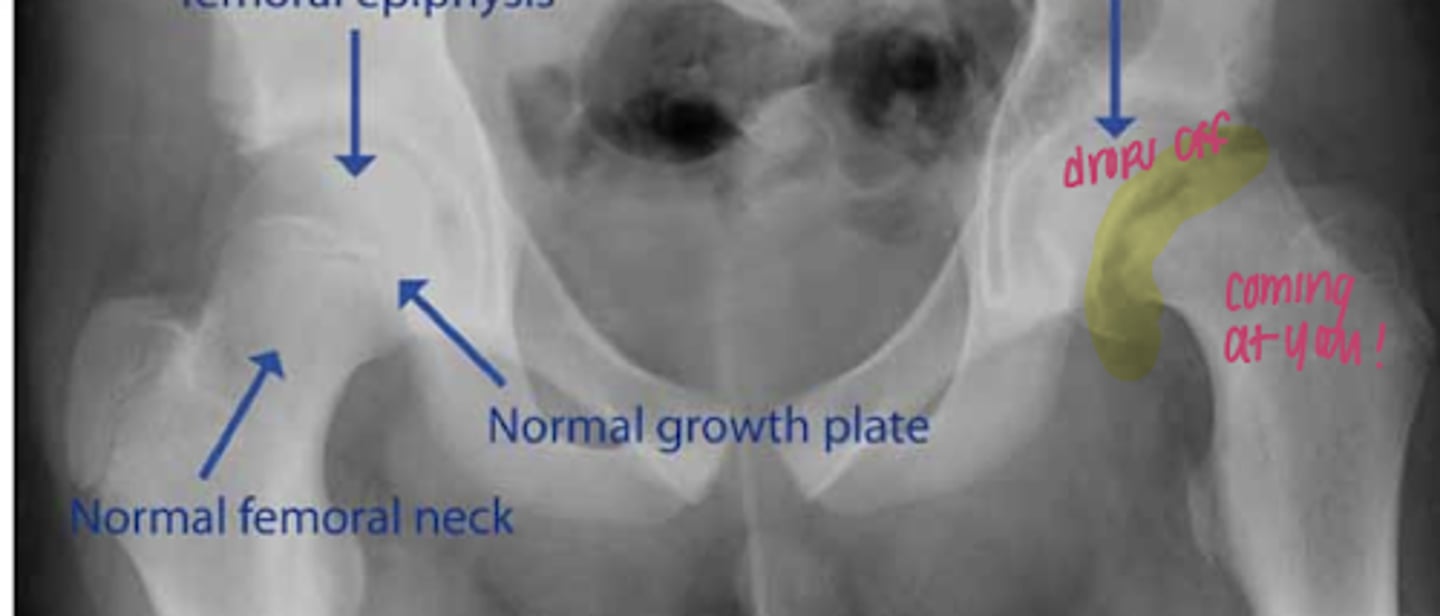

SCFE

percutaneous pinning for SCFE